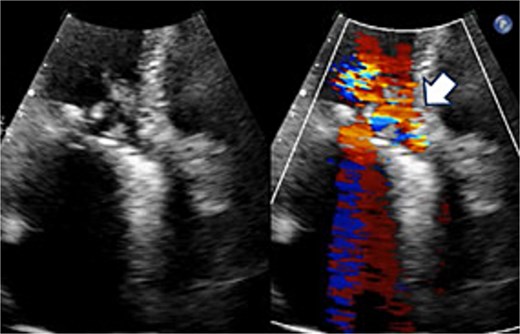

A 70-year-old woman (body surface area [BSA] 1.42 m2) had undergone aortic valve replacement (St. Jude Medical 19 mm mechanical aortic valve; Abbott, St. Paul, MN, USA), mitral valve repair (Physio Ring 24 mm; Edwards Lifesciences, Irvine, CA, USA), and tricuspid annuloplasty with De Vega technique 13 years earlier. Over the previous two years, she experienced progressive heart failure despite optimized medical therapy. Echocardiography demonstrated severe mitral stenosis with a mitral valve area of 0.96 cm2, markedly restricted leaflets, and calcification of both commissures. The aortic prosthesis showed a peak velocity of 3.3 m/s with moderate stenosis and moderate paravalvular regurgitation (Fig. 1). Given persistent symptoms and limited efficacy of medical management, surgical intervention was planned. Her comorbidities included hypertension and chronic atrial fibrillation.

Preoperative transthoracic echocardiography: significant paraventricular leakage was shown with the white arrow.